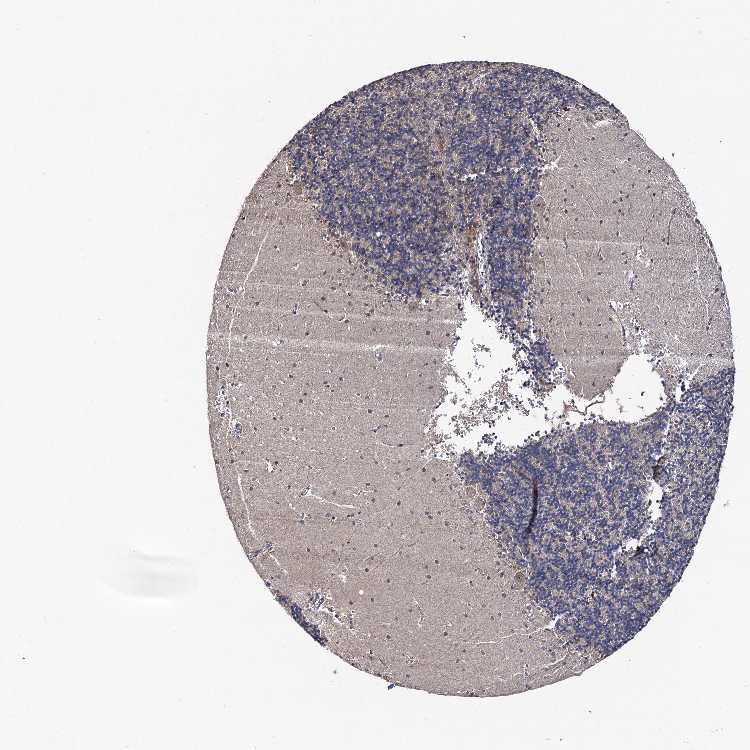

CEREBELLUM - Antibody stainingi

Antibody staining in the annotated cell types in the current human tissue is reported as not detected, low, medium, or high, based on conventional immunohistochemistry profiling in selected tissues. This score is based on the combination of the staining intensity and fraction of stained cells.

Each image is clickable and will lead to virtual microscopy that enables deeper exploration of all samples and also displays staining intensity scores, fraction scores and subcellular localization as well as patient and tissue information for each sample.

Antibody HPA039318Antibody HPA039763

Purkinje cells MediumLow

Cells in granular layer Not detectedNot detected

Cells in molecular layer LowMedium